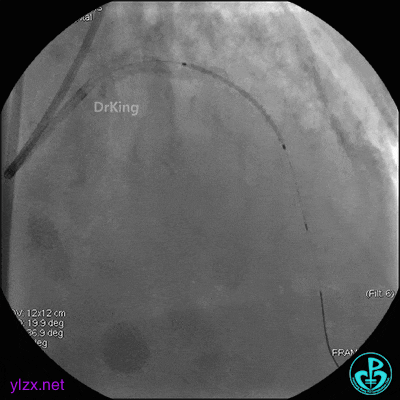

4 急诊冠脉造影

左主干轻度狭窄,左主干到前降支近端钙化影明显。前降支开口严重狭窄,近端闭塞。粗大回旋支轻度狭窄。

右冠脉无严重狭窄,右冠脉没有给前降支提供逆向供血。

5 治疗过程

EBU指引导管到位,导丝通过闭塞段到达前降支远端,经指引导管冠脉内推注替罗非班6ml,前降支恢复3级血流,闭塞段局部残余狭窄严重,2.0×15mm球囊扩张前降支近端闭塞处后再次冠脉内推注替罗非班8ml。下台继续治疗。